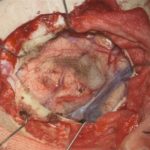

No.’25_108 摘出 前

No.’25_108  摘出 中

No.’25_108 摘出 後

右頭頂葉腫瘍

頭蓋内腫瘍摘出術

No.’25_108 手術前1

No.’25_108 手術前2